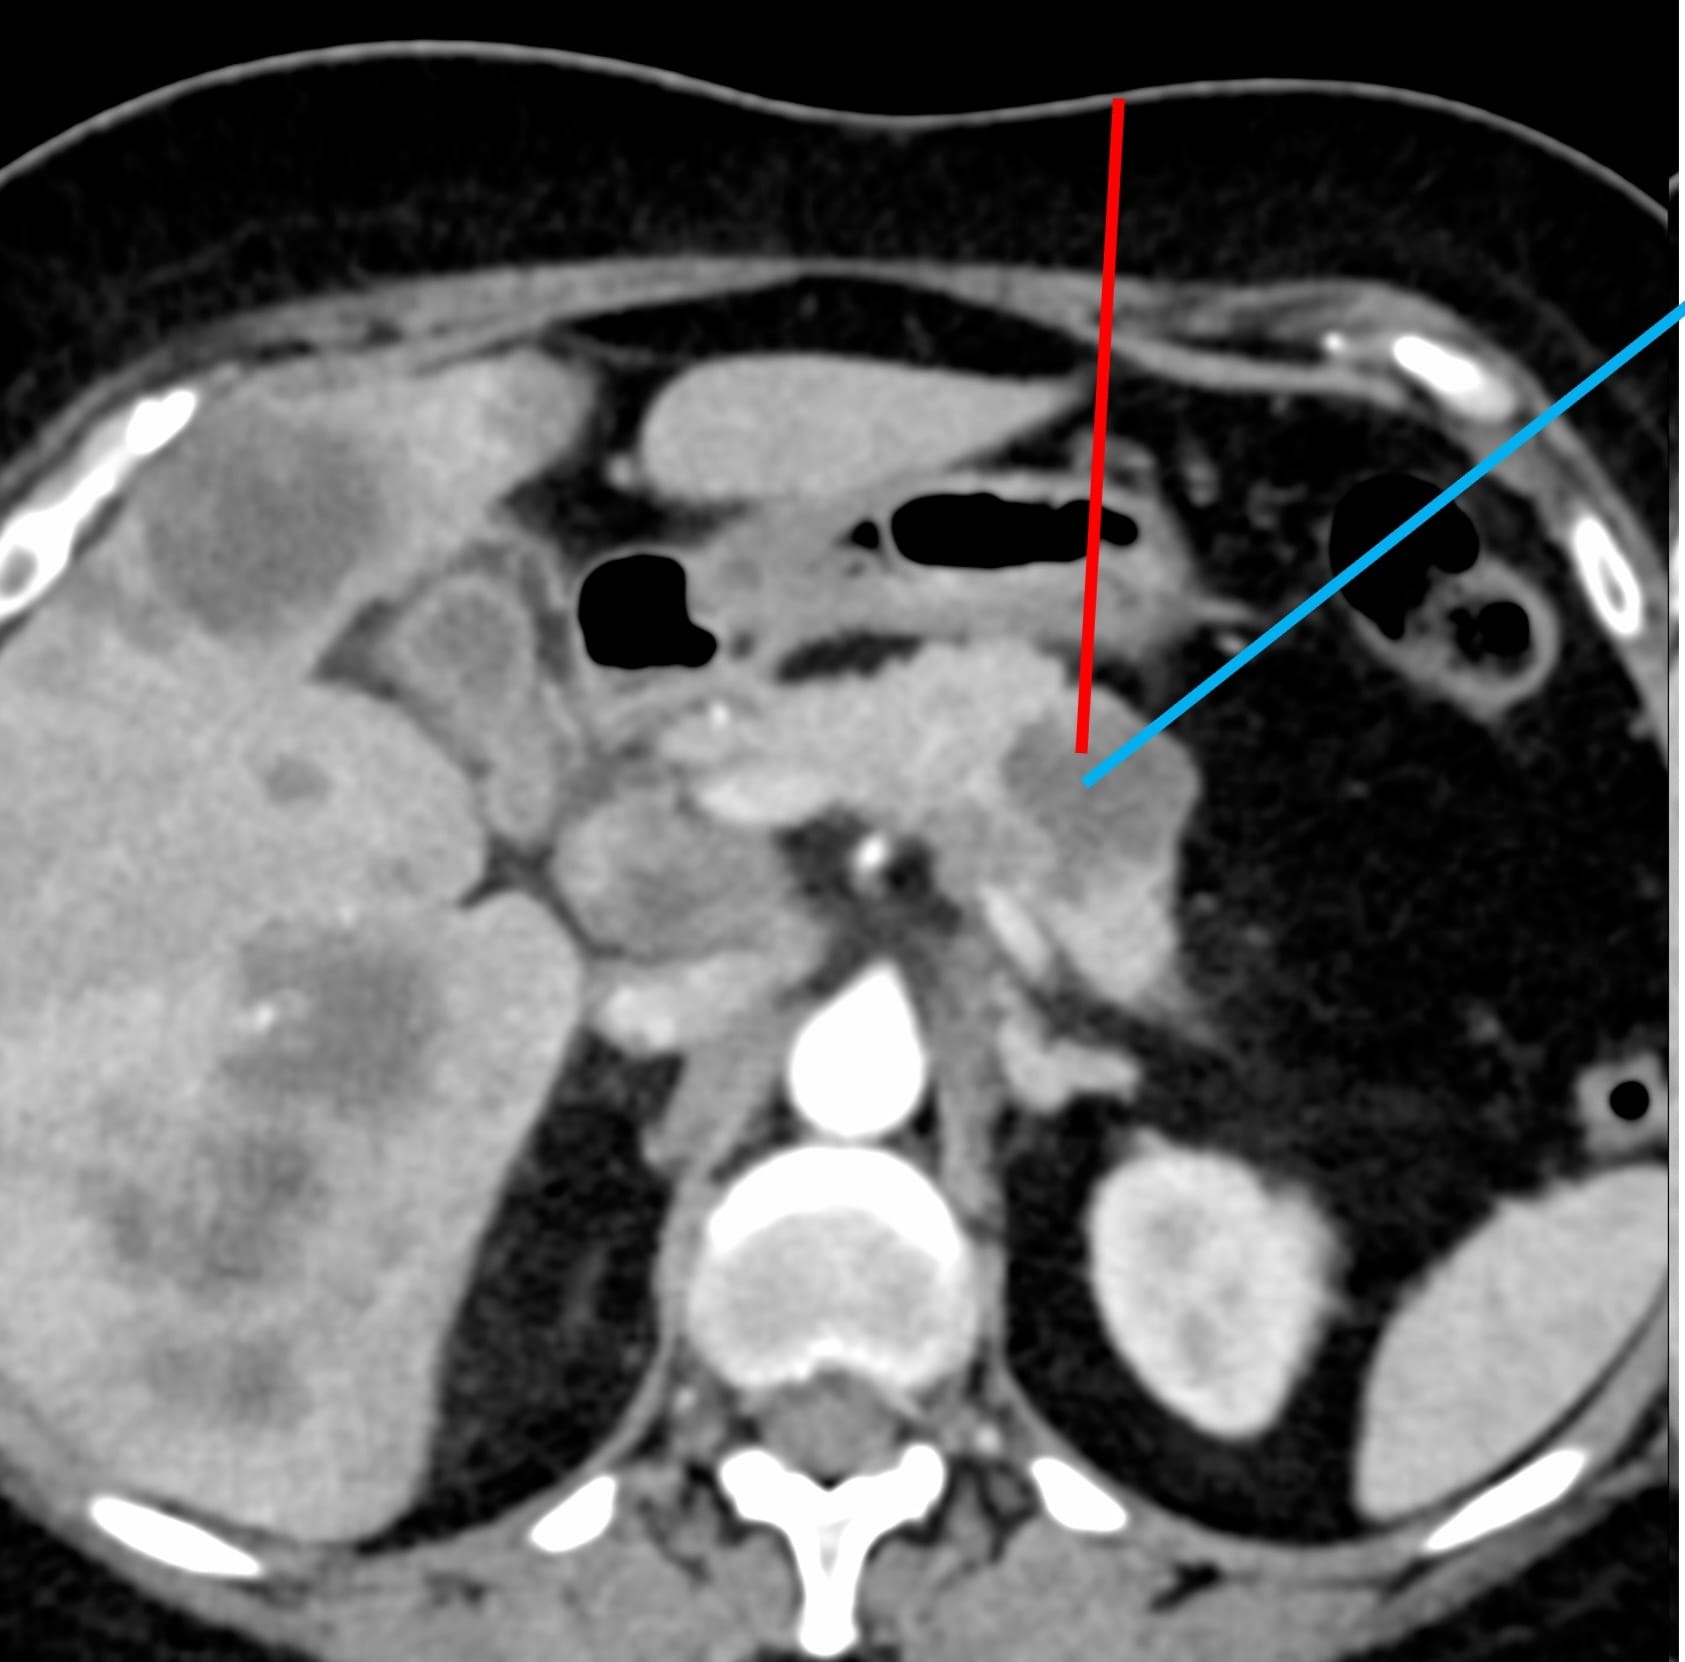

A 55-yrs old presented with a pancreatic body mass and liver lesions.

USG guided liver lesion biopsy was negative and the oncologist wanted a biopsy from the pancreatic body lesion.

What route will you take?